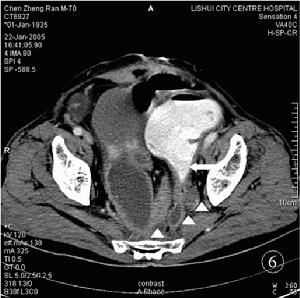

粘連性腸梗阻

急性粘連性腸梗阻主要是小腸機械性腸梗阻的表現,

病人多有腹腔手術、創傷或感染的病史,以往有慢性腸梗阻症狀和多次急性發作者多為廣泛粘連引起的梗阻;長期無症狀,突然出現急性梗阻症狀,腹痛較重,出現腹部局部壓痛,甚至腹肌緊張者,即應考慮是粘連帶等引起的絞窄性腸梗阻。 手術後近期發生的粘連性腸梗阻應與手術後腸麻痹恢復期的腸蠕動功能失調相鑑別,後者多發生在手術後3—4日,當自肛門排氣排便後,症狀便自行消失。治療